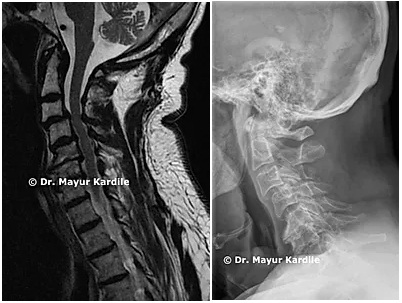

Anterior Cervical Discectomy & Fusion

ACDF

Anterior Cervical Discectomy and Fusion to treat cervical radiculopathy, disc herniation, and nerve compression in the neck.